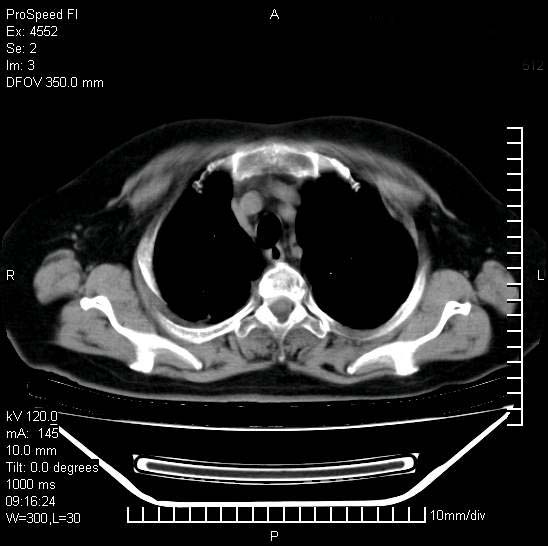

标题: CT15528:女性,79岁,近几日晚上高热,39度,仍咳少量血 [打印本页]

十几年前曾患肺结核,一周前突咳血约100ml,中性粒细胞稍高,诊断两上肺陈旧结核,下肺炎症,给予抗炎治疗,近几日晚上高热,39度,仍咳少量血,4天前ct及今天ct上传。

[face=黑体]8月30日[/face]

支持陈旧性肺结核并两下肺感染,两侧胸腔积液。

考虑1双肺tb灶;右下肺支气管壁增后,建议除外占位 3双侧胸腔积液,

短短几天内,病变范围明显增多扩大,以左侧明显,而且双侧出现胸水,还是考虑感染.

1)两肺结核并感染。2)不排除左肺上叶中央型肺癌并阻塞性肺炎、肺不张可能;建议行纤支镜检查。3)右肺门及纵隔淋巴结肿大。4)双侧胸腔积液。

陈旧性肺结核及左下肺不张,咯血后肺部感染,双胸腔积液,高热可能与痰液引流不畅有关。